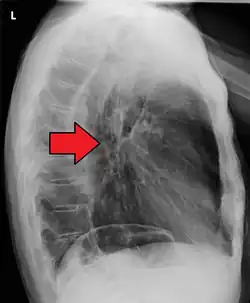

Additional testing is needed to assess how much the cancer has spread (see § Staging, below). Computed tomography (CT) of the chest, abdomen and pelvis can evaluate whether the cancer has spread to adjacent tissues or distant organs (especially liver and lymph nodes). The sensitivity of a CT scan is limited by its ability to detect masses (e.g. enlarged lymph nodes or involved organs) generally larger than 1 cm.[44][45] Positron emission tomography is also used to estimate the extent of the disease and is regarded as more precise than CT alone.[46] PET/MR as a novel modality has shown promising results in preoperative staging with fair feasibility and good correlation in comparison to PET/CT. It can enhance tissue differentiation with lowering the radiation dose to the patient.[47] Esophageal endoscopic ultrasound can provide staging information regarding the level of tumor invasion, and possible spread to regional lymph nodes.